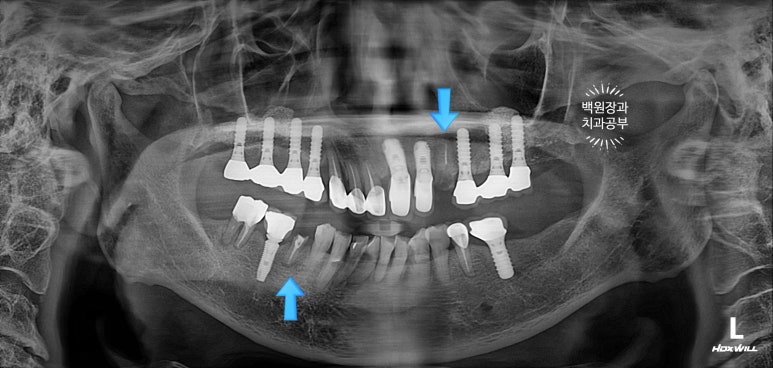

처음 오셨을 때, 치과용 파노라마 사진에서 파란색 화살표로 표시해둔 두 치아 - 왼쪽 위 송곳니와 오른쪽 아래 작은어금니가 뿌리만 남아있는 상태로 내원하셨어요.

특이할만한 점이, 두 치아 모두 신경치료와 크라운 치료를 받았던 치아였다는 것... 역시나 신경치료는 치아 건강에 그리 좋지 않음을 알 수 있습니다..

아까 말씀드렸듯, 왼쪽 위 송곳니와 오른쪽 아래 작은어금니에 뿌리만 있는 잔존치근이 관찰됩니다.

개인적으로 이를 뽑으면서 동시에 심어내는 발치 즉시 임플란트에 보수적인 의사입니다만,

이렇게 비록 치아가 썩어서 부러졌을지언정 만성치주염없이 건강한 잇몸뼈를 가지신 분은 충분히 고려해볼만 하죠!!